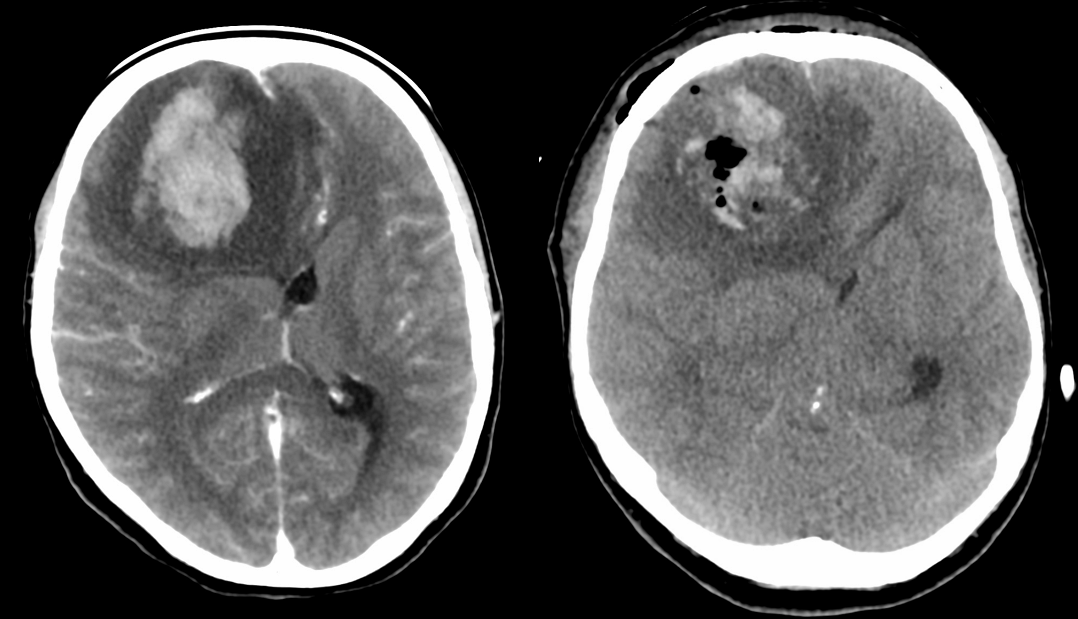

Este investigată la spitalul local prin CT cerebral cu contrast, care evidențiază un hematom intracerebral frontal drept de cca 4 cm diametru, cu important efect de masă, și herniere subfalcină de girus cinguli; aspectul polului frontal adiacent hematomului (hipodens) este interpretat ca edem cerebral. Se intervine chirurgical și se evacuează hematomul, fără prelevarea unei biopsii.

Se reface imagistica – de aceasta dată RMN cerebral cu contrast – și se constată prezența unei tumori cerebrale infiltrative de cca 7/7/6 cm, în cea mai mare parte negadolinofila, hipo-T1, hiper-T2 și FLAIR, cu zone hemoragice la interior și efect de masă important – deplasarea structurilor liniei mediene cu 2 cm, hernie de girus cinguli și hidrocefalie internă prin obstrucția formen Monro – imagine sugestivă pentru un gliom de grad înalt, cel mai probabil glioblastom.